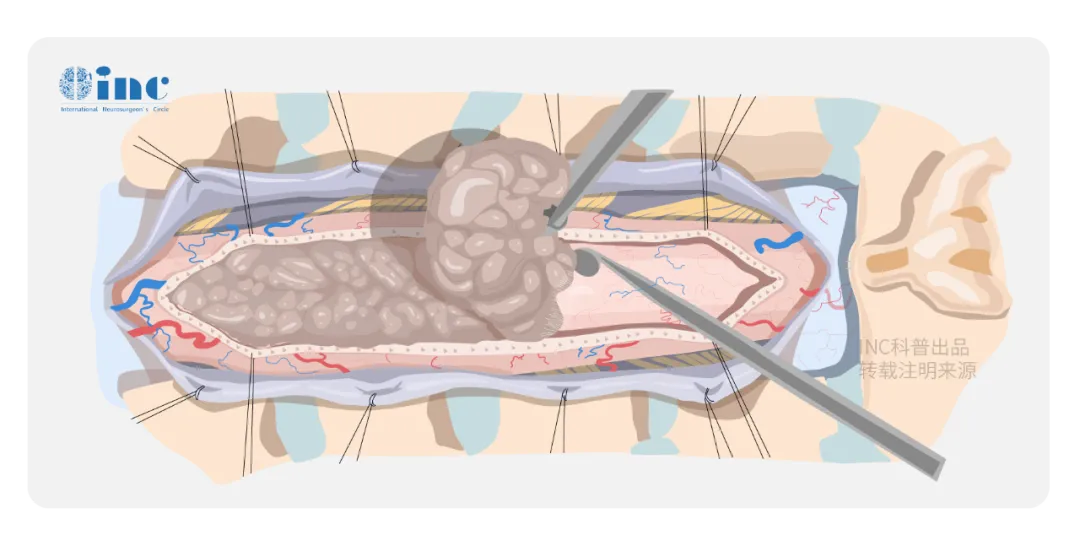

脊髓作为连接大脑与周围神经系统的主要通路,密布31个脊髓神经节和来自脑干的四条运动神经束。而如果肿瘤生长在脊髓内,位置处于外科手术的“禁区”:所在区域部位深、被脊骨包围、暴露困难,脊髓是很娇嫩的组织,稍受挤压或碰撞,即可造成永久性的障碍,下肢瘫痪、大小便失禁等。如果两侧的神经根如果出现破损,病人也可能出现瘫痪。手术后可能会瘫痪是根植在每一个罹患脊髓髓内肿瘤患者心中深处的恐惧。

手术中怎么办才能避免对脊髓的损伤吗?

电生理监测可在诸多方面有助于神经外科医生的判断。每例脊髓肿瘤手术均应进行持续同步的术中感觉诱发电位(SEPs)和MEPs监测,并由专职的神经生理学家操作。第一,使医生易于鉴别神经结构,特别是对于那些因肿瘤、外伤或以前的手术已使脊髓结构发生改变的病例;第二,可指导手术切除病变的程度和范围,以便保护神经功能;第三,可有助于确定病变在传导功能受损神经上的解剖定位。

“根据我的手术经验,在保留脑干和脊髓中运动感觉神经功能的前提下,手术是可行的。手术中必须要有电生理监测。”